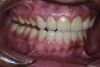

Figure 3. Preoperative 1:2 retracted right lateral view.

Figure 3

Figure 4. Preoperative 1:2 retracted left lateral view.

Figure 4

A thorough clinical examination and analysis were carried out to assess the esthetic and functional problems of the patient (Figure 2 through Figure 7). The medical history was non-contributory, except for mild leukoderma. Temporomandibular joint (TMJ) function was within normal range.